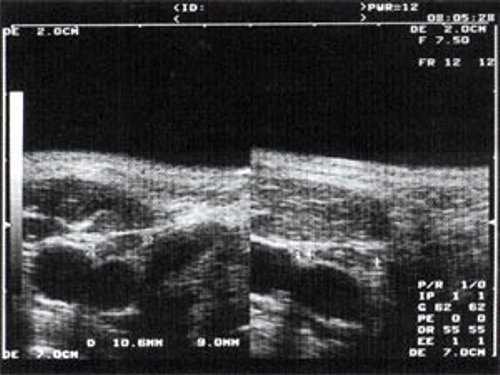

Практически во всех случаях дифференцировали лимфатический узел Кютнера (югулодигастральный), расположенный на границе средней и верхней трети шеи. Выявляемые лимфатические узлы имели размеры от 0,5 х 0,2 см до 2,3 х 0,8 см. УЗ-оценку производили после полипозиционного осмотра и нахождения самой длинной горизонтальной оси, что и принимали за максимальный поперечный диаметр. Большая часть лимфатических узлов (187) имели овальную форму с соотношением поперечного/переднезаднего более 1 (рис. 1 - 3). Тенденцию к округлению имели 30 лимфатических узлов, соотношение поперечного/переднезаднего приближалось к 1.

Рис. 3. Эхографическое изображение непальпируемого югулярного лимфатического узла без четкой клинической симптоматики воспалительного процесса в области головы и шеи.